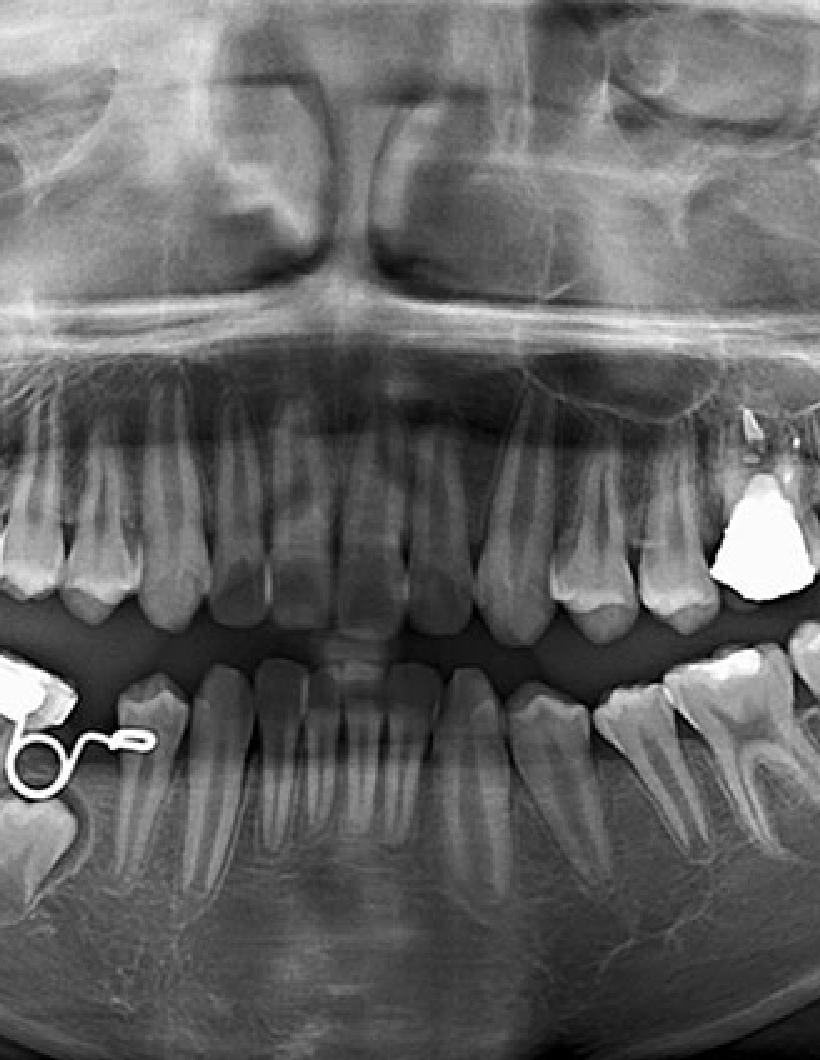

La radiologie dentaire 3D est devenue une alliée incontournable pour le diagnostic et la planification des soins complexes. Avec notre gamme de panoramiques numériques, vous accédez à une imagerie haute définition en quelques secondes, tout en réduisant les doses d’exposition pour le patient.

Jusqu’à 90 µm de précision pour des diagnostics cliniques sûrs.

Pour planifier et sécuriser vos chirurgies grâce à des coupes 3D précises.